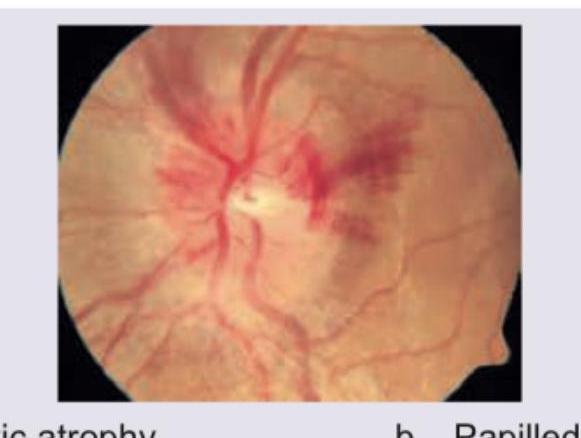

The fundus shown below indicates presence of:

Explanation: ***Papilledema*** - The image shows a **swollen optic disc** with blurred margins, loss of the optic cup, and **hemorrhages** on and around the disc, all characteristic features of papilledema. - **Papilledema** is swelling of the optic disc due to increased intracranial pressure. *Optic atrophy* - **Optic atrophy** typically presents with a **pale optic disc**, sharply defined margins, and a reduction in the number of retinal nerve fibers. - There is no evidence of disc pallor or sharp margins in the provided image; instead, there is significant disc swelling and blurring. *Cupping of the disk* - **Cupping of the disc** refers to an enlargement of the physiological optic cup, often seen in glaucoma where there is a backward displacement of the lamina cribrosa. - The image clearly shows **loss of the optic cup** due to swelling, not an enlargement of it. *Silver wire appearance* - The **silver wire appearance** refers to a prominent light reflex off the blood column in retinal arterioles, indicating severe arterial narrowing and sclerosis, typically seen in advanced hypertensive retinopathy. - The primary findings in this image relate to the optic disc and surrounding tissue, not the general appearance of the retinal arterioles.